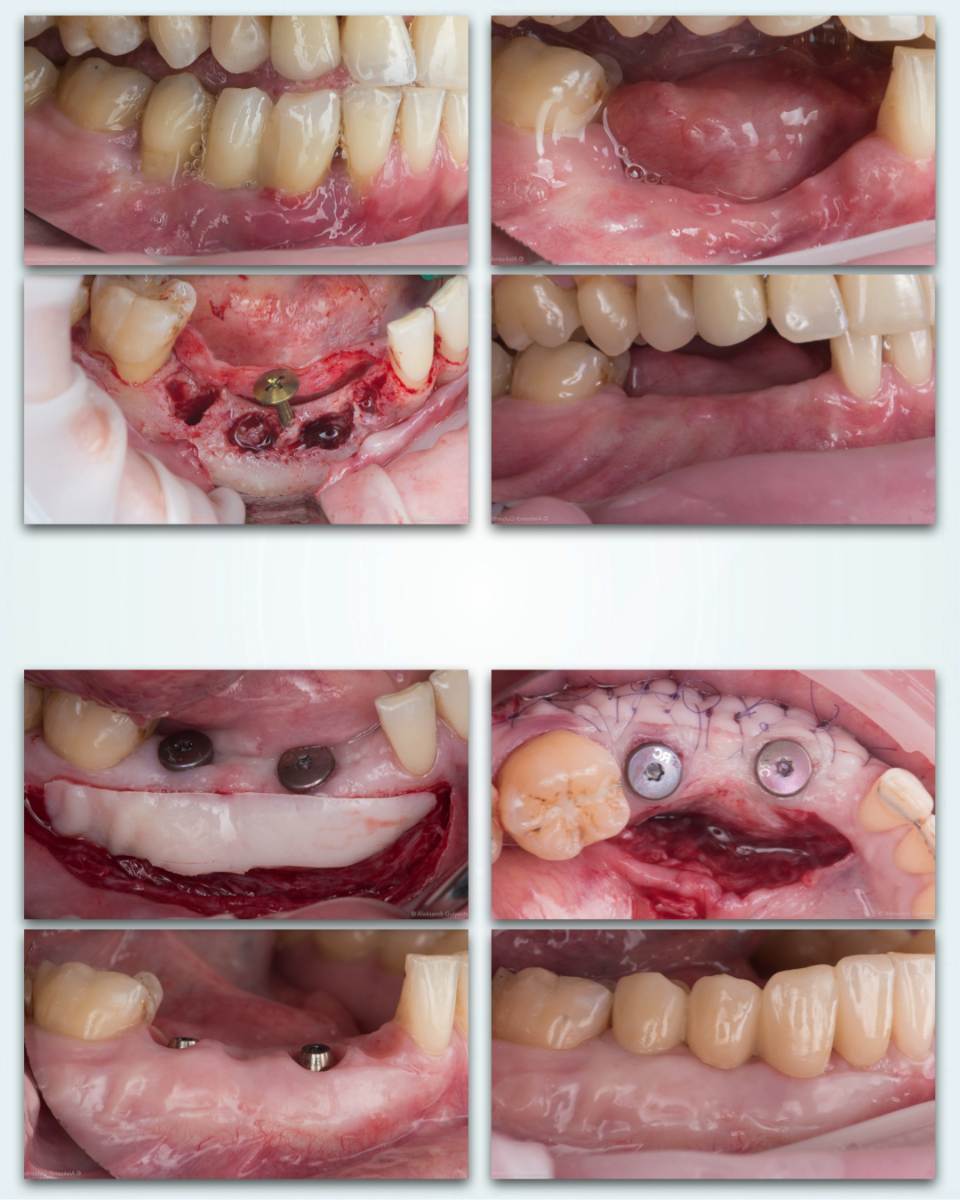

stommm Опубликовано 28 сентября, 2024 Поделиться Опубликовано 28 сентября, 2024 Всем доброго времени суток. История длиною в 2 года 9 месяцев. Ортопед Залим Иругов, техник Виталий Шамин. Приятного просмотра) 10 1 1 Ссылка на комментарий

stommm Опубликовано 29 сентября, 2024 Автор Поделиться Опубликовано 29 сентября, 2024 1 час назад, Aquarius сказал: Браво!! Блестящая работа, доктор!! Скажите , донорские зоны такого масштаба ведёте под капой? Спасибо не пользуюсь каппами. Композитная повязка и швы 9 минут назад, Тимур86 сказал: Крутяк! Фото сочные. Зачем тент под титановую мембрану? Спасибо что бы мембрану было проще по высоте стабилизовать. Но в итоге он встал ниже чем хотелось, лунки плохо зажили. Так что не особо помог Ссылка на комментарий

stommm Опубликовано 29 сентября, 2024 Автор Поделиться Опубликовано 29 сентября, 2024 8 минут назад, Женька сказал: чья сетка и чем шили уже спрашивали?) Сетка вроде Пенза. Винты (кроме тентового) точно их. Швы 1 птфэ, остальное эльмонк 6-0 или моноквик 6-0. Может ещё 7-0 пдо где-то был, не помню. 2 1 Ссылка на комментарий

stommm Опубликовано 29 сентября, 2024 Автор Поделиться Опубликовано 29 сентября, 2024 Точно делал заранее, но что-то не понравилось и то ли переделывал интраоперационно, то ли ту подкорректировал. Не вспомню точно уже. Давно было) Ссылка на комментарий

stommm Опубликовано 29 сентября, 2024 Автор Поделиться Опубликовано 29 сентября, 2024 10 минут назад, Женька сказал: @Doc плюс вторичные деформации могут образовывать ведь? Как считаете, капа спасёт от этого? Я думаю, Николай про этап, где СДТ подсаживали. Мне тоже интересно, как определяете, что язычно уже надо остановиться? Где уже совсем стало страшно, остановился) Я рутинно язычно сдт не фиксирую, но главное слишком глубоко не уходить и углубляться очень медленно и аккуратно. Если гребень реконструирован, это проще. После редукции под фп3 сложнее Ссылка на комментарий

stommm Опубликовано 29 сентября, 2024 Автор Поделиться Опубликовано 29 сентября, 2024 (изменено) Во время костной пластики на столько, сколько нужно для закрытия дефект. Аккуратно, тупым способом. Вмэто случай даже допразрез язычно был, хотя обычно их не делаю 1 минуту назад, Irouil сказал: У нас в клинике, в силу специфики приема, мульты используются "не просто смело, а пи***ц как смело" ©️, в том числе на таких двух-трех опорных мостах. В отдалённой перспективе столкнулись с массовыми раскручиваниями, соединение то слабенькое, поэтому сейчас принцип другой - гибридный уровень протезирования, мульт для пассивации, а второй имплант с платформы На какой системе/системах работаете? Раскручиваются сами мульты или коронки? Изменено 29 сентября, 2024 пользователем stommm Ссылка на комментарий